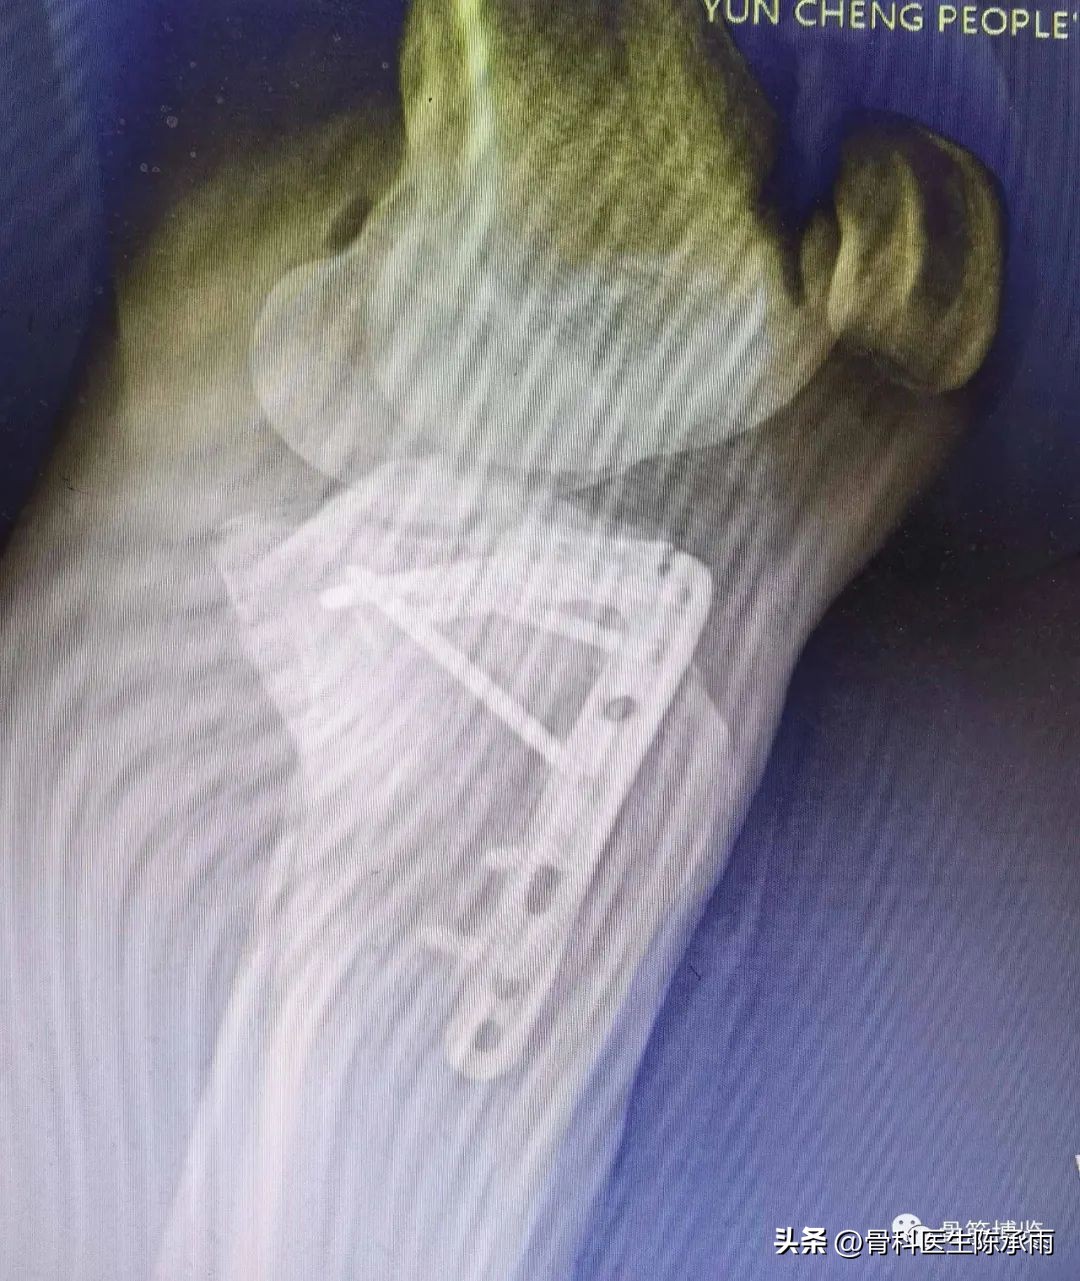

1例

2例

3例

4例

5例

6例

7例